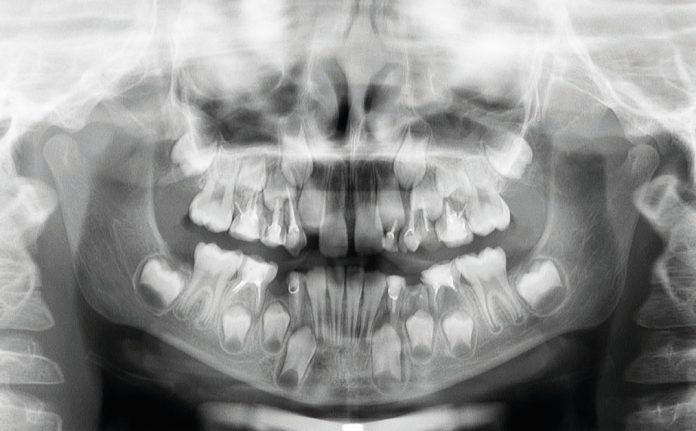

Tale affermazione è stata dimostrata dall’analisi dell’ortopantomografia, in cui era evidente la presenza di materiale non riassorbile, presumibilmente materiale di otturazioni canalari per elementi definitivi, utilizzato in questo caso clinico in elementi dentali decidui, con conseguente difficoltà nel processo di esfoliazione e riassorbimento delle radici stesse (fig. 1).

Terminata la prima fase, all’età di 11 anni, il paziente è stato rivalutato tramite gli esami radiografici. Dall’OPT si osservava la presenza della dentatura permanente, con prossima esfoliazione dei settimi, oltre alla formazione delle gemme degli elementi 18-28-38-48 (fig. 4).